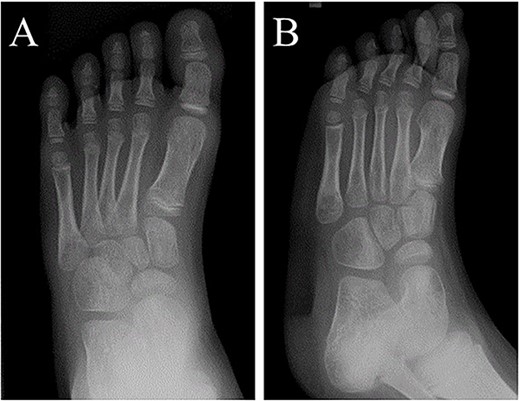

A 21-month-old Japanese female infant presented with a swollen mass on the dorsolateral aspect of the left foot. Her parents noticed the mass and brought the patient to our hospital. The patient had no past medical histories or complications prior to the occurrence. In addition, she received the BCG vaccine at the age of 4 months in Japan. At first visit to our hospital, physical examination revealed the ~3 × 3 cm mass was located on the dorsolateral aspect of the left foot and was hard accompanied by local heat (Fig. 1). Plain radiographs of the left foot showed a lytic lesion without periosteal reaction in the fifth metatarsal bone (Fig. 2). Magnetic resonance imaging (MRI) showed an isointense lesion on T1-weighted images and a hyperintense lesion on T2-weighted images around and within fifth metatarsal (Fig. 3). Gallium scintigraphy revealed intense uptake in the patient’s left foot (Fig. 4). In addition, laboratory examination was within normal. Based on medical history, clinical and imaging findings, we considered the possibility of neoplasia or osteomyelitis and performed an open debridement and biopsy of the lesion to make a diagnosis. The lesion was yellow and consisted of weak, adipose-like tissue that surrounded and continued into the inferior of the fifth metatarsal bone (Fig. 5). The lesion inside and outside the bone was resected as much as possible. Histopathologic examination of the lesion showed granulomatous inflammation including anaplastic giant cells, Langerhans-type giant cells and caseous necrosis (Fig. 6). Based on these results, TB or BCG osteomyelitis was considered as a diagnosis. The tuberculin test was positive, but the QuantiFERON TB test was negative. In addition, samples analyzed using polymerase chain reaction did not identify M. tuberculosis, but did identify the BCG Tokyo-172 strain. Per these findings, the patient was diagnosed with BCG osteomyelitis of the fifth metatarsal and oral treatment with anti-TB medicine including isoniazid (100 mg/day) and rifampicin (150 mg/day) was started. Clinical findings included reduction in swelling of the mass and gradual remodeling of the lytic lesion of the fifth metatarsal on plain radiographs (Fig. 7). However, 10 months after starting the anti-TB treatment, the mass recurred, and MRI revealed a residual high-intensity lesion around and inside the fifth metatarsal on T2-weighted fat-suppressed images (Fig. 8). It was determined that the lesion was difficult to control with anti-TB treatment alone, so an open debridement for the lesion was performed again. Histopathologic examination of the lesion revealed an epithelioid granuloma with necrosis. Therefore, the anti-TB treatment was continued. Six months after the second surgery, clinical and radiographic image findings showed complete improvement (Fig. 9). As a result, anti-TB treatment was ended. At the time of writing this report, 8 years after starting anti-TB treatment, there has been no recurrence.

Plain radiographs of the left foot showing a lytic lesion without periosteal reaction in the fifth metatarsal bone in (A) anteroposterior and (B) oblique views.

Plain radiographs of the left foot showed the lytic lesion of the fifth metatarsal was remodeled gradually in (A) anteroposterior and (B) oblique views.

At 6 months after the second surgery, image findings on plain radiographs completely improved on (A) anteroposterior and (B) oblique views.